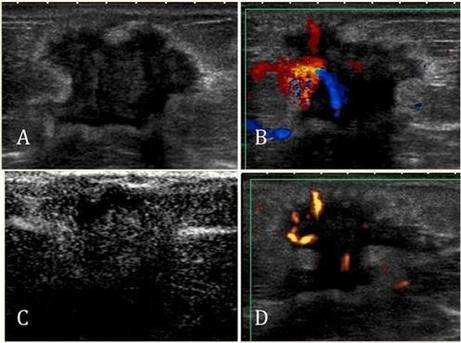

Memede saptanan kitlelerin ultrasonu özelliklerinin değerlendirilmesi ile iyi huylu, kötü huylu ya da şüpheli olduğu söylenebilir. İyi huylu kitlelerin normal meme dokusuna göre kötü huylu kitlelerle dönüşmesinin riski daha yüksek olduğu için 3 ya da 6 ay aralıklarla meme ultrasonu ile takip edilmelidir. Şüpheli kitlelerin kısa aralıkla takibi, mamografi ve meme MRG ile değerlendirilmesi gerekebilir. Meme ultrasonunda büyük olasılıkla kötü huylu olduğu düşünülen kitleler için ise meme ultrasonu eşliğinde biyopsi yapılması gerekecektir.